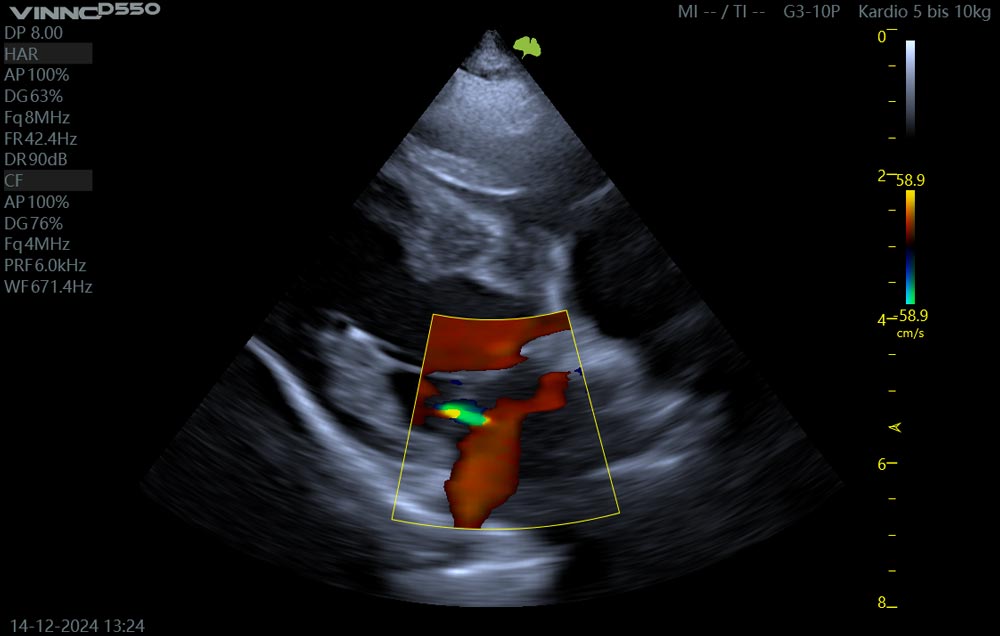

Die Untersuchung des Herzens mittels Ultraschall, Echokardiographie genannt, ermöglicht eine präzise Darstellung der Herzstrukturen und der Herzleistung. Wir können die Herzklappen der beiden Kammersysteme genau darstellen, ihre Dichtigkeit mit dem Farbdoppler untersuchen und die Auswurfleistung des Herzens mit dem Spektraldoppler hochauflösend darstellen. Ein mitlaufendes EKG zeigt genau, wann sich Klappen schließen, wie sich der Herzmuskel kontrahiert und vieles mehr.